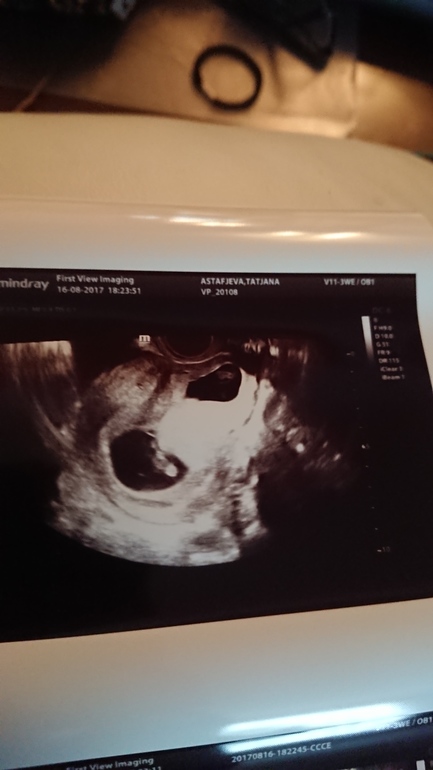

Как мне объяснила узистка узи наоборот показывает. То есть то которое на фотке верхнее, оно и есть нижнее, которое сейчас 'уходит'. Оно и на сегодняшней фотке меньше чем второе.

А вот неделю назад